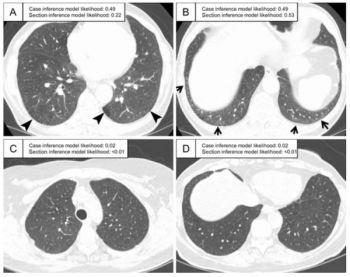

A machine-learning-based model demonstrated an 87 percent area under the curve and a 90 percent specificity rate for predicting interstitial lung abnormality on CT scans, according to new research.